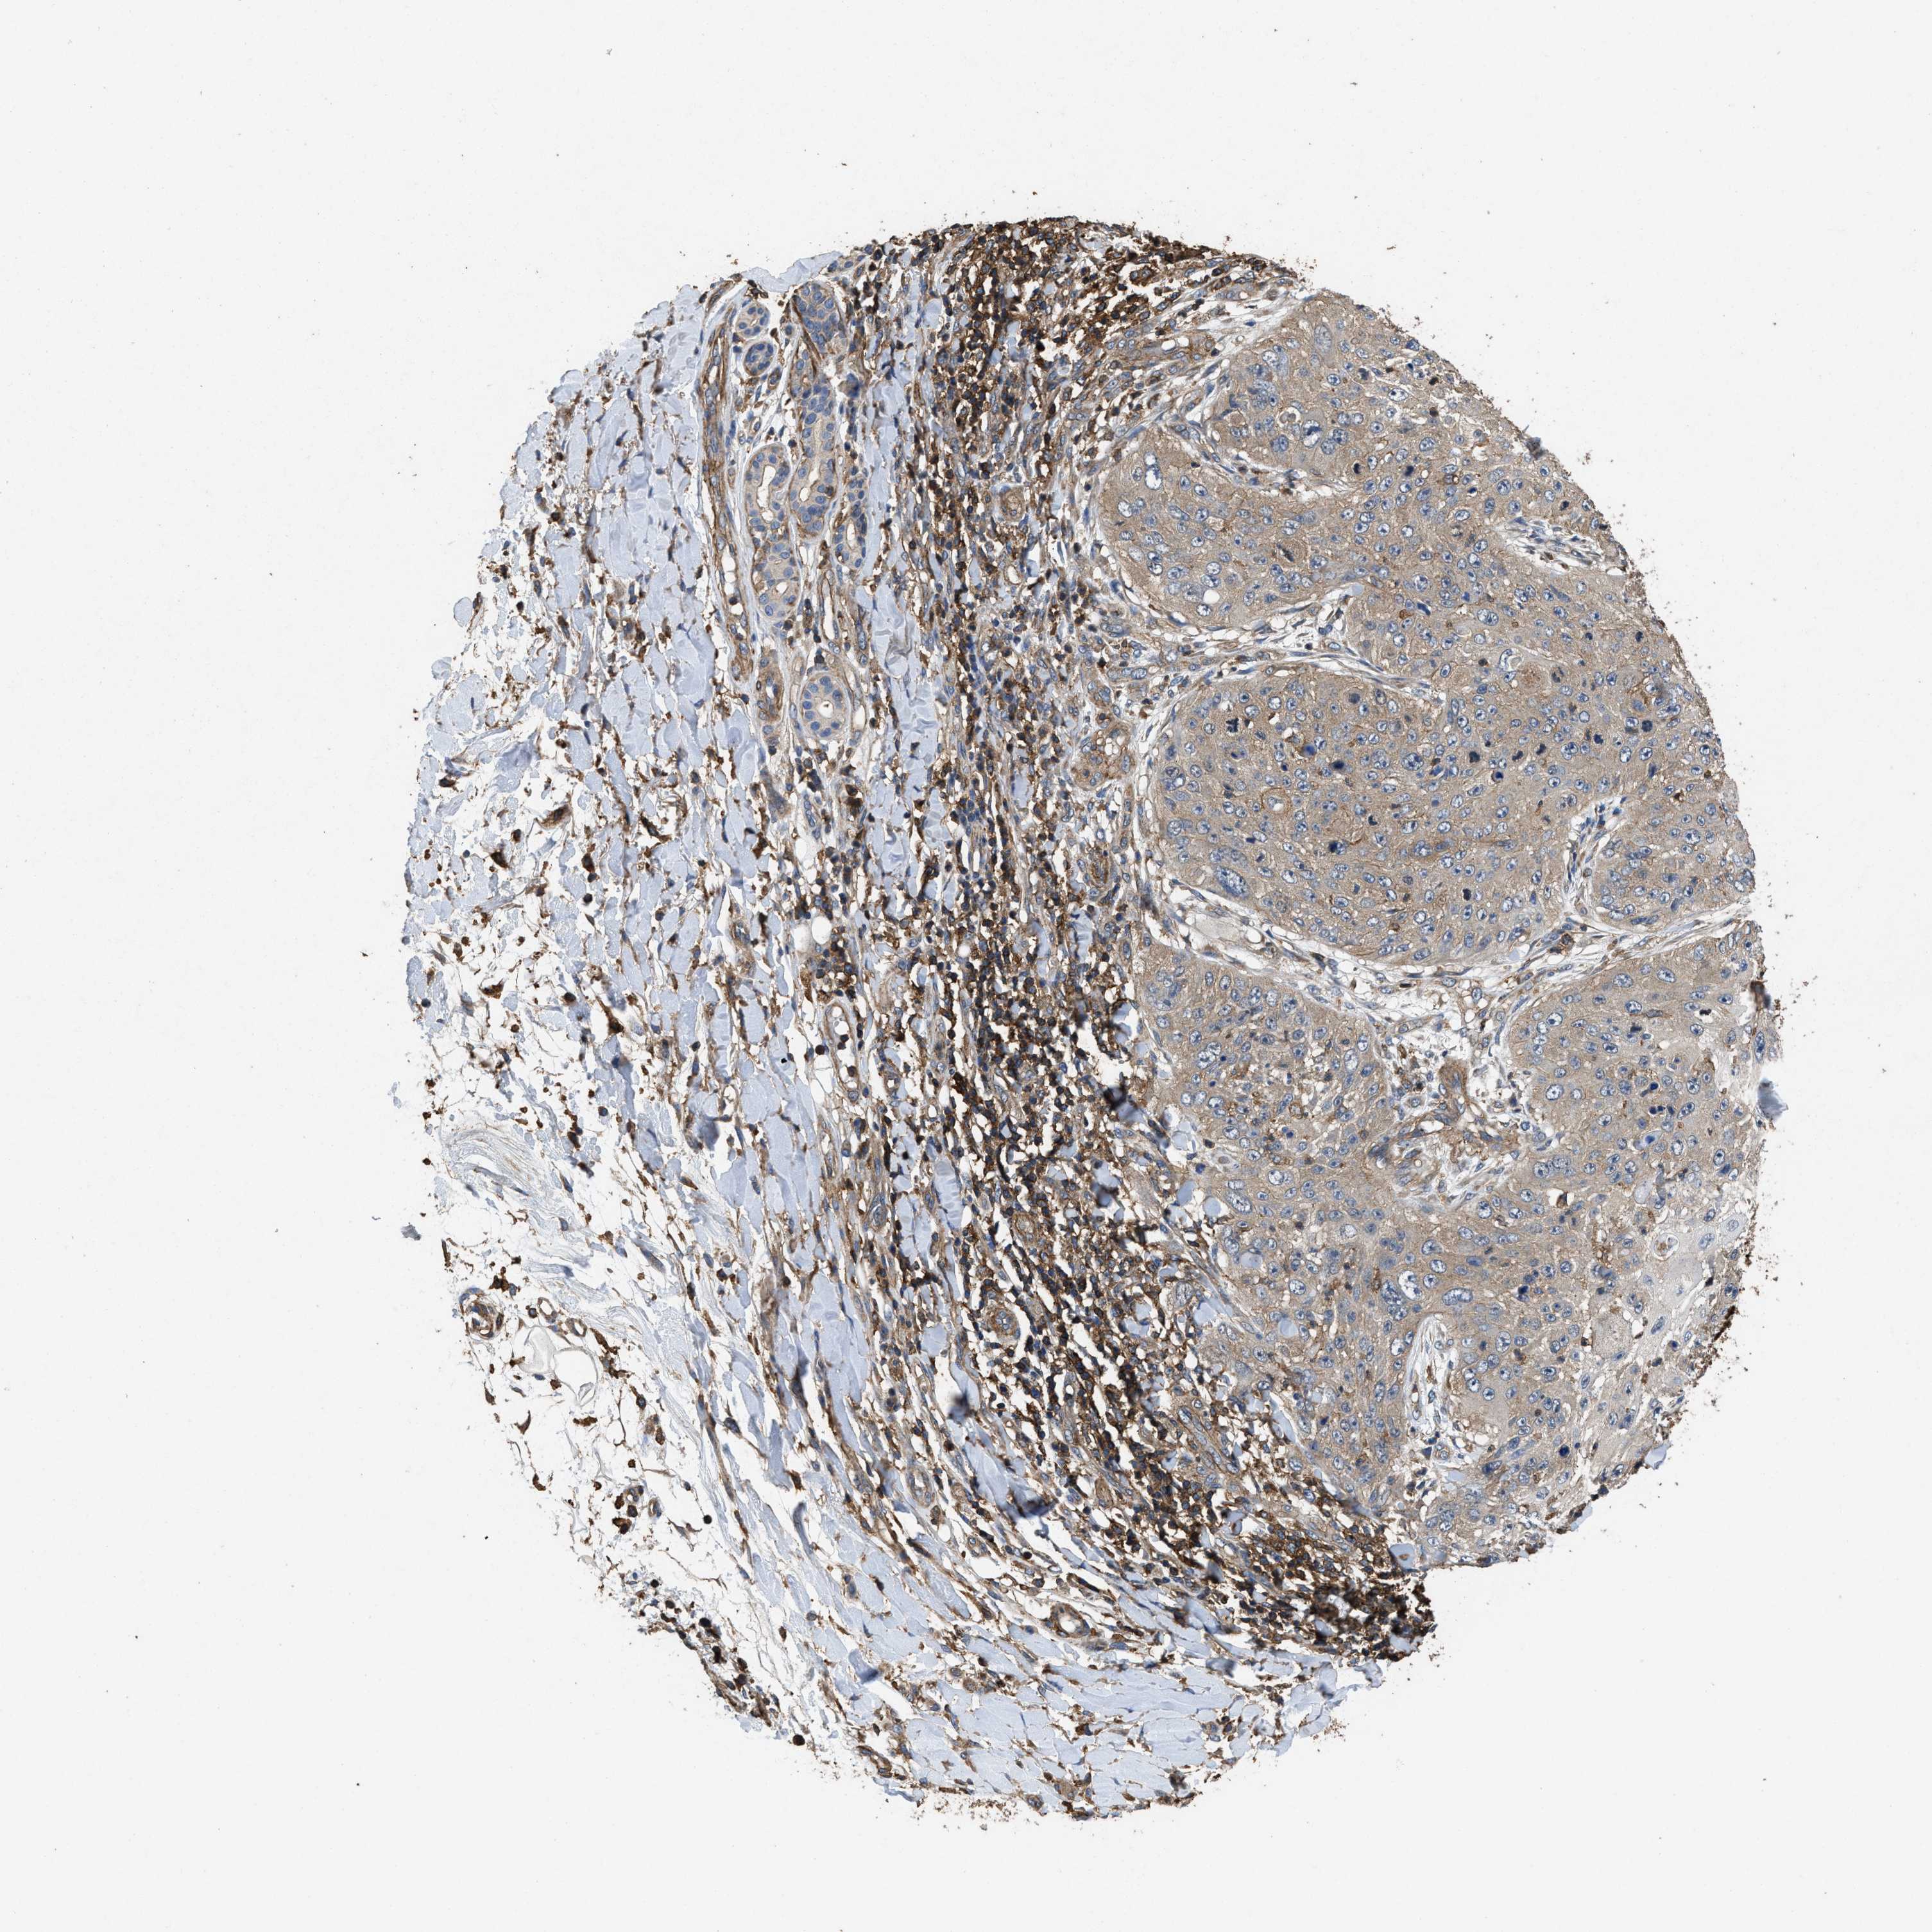

SKIN CANCER - Protein expressioni

A mouse-over function shows sample information and annotation data. Click on an image to view it in a full screen mode. Samples can be filtered based on level of antibody staining by selecting one or several of the following categories: high, medium, low and not detected. The assay and annotation is described here.

Antibody stainingi

Antibody staining in the annotated cell types in the current human tissue is reported as not detected, low, medium, or high, based on conventional immunohistochemistry profiling in selected tissues. This score is based on the combination of the staining intensity and fraction of stained cells.

Each image is clickable and will lead to virtual microscopy that enables deeper exploration of all samples and also displays staining intensity scores, fraction scores and subcellular localization as well as patient and tissue information for each sample.

Antibody CAB025361

Squamous cell carcinoma, metastatic, NOS